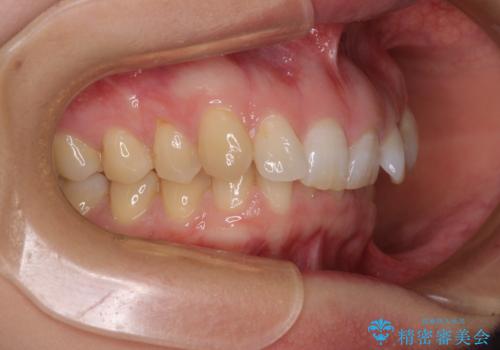

カリエール・ディスタライザーとインビザラインを用いた前歯の咬み合わせ改善

- 1年10ヶ月